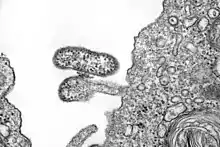

| electron microscope image of Chapare virus | |